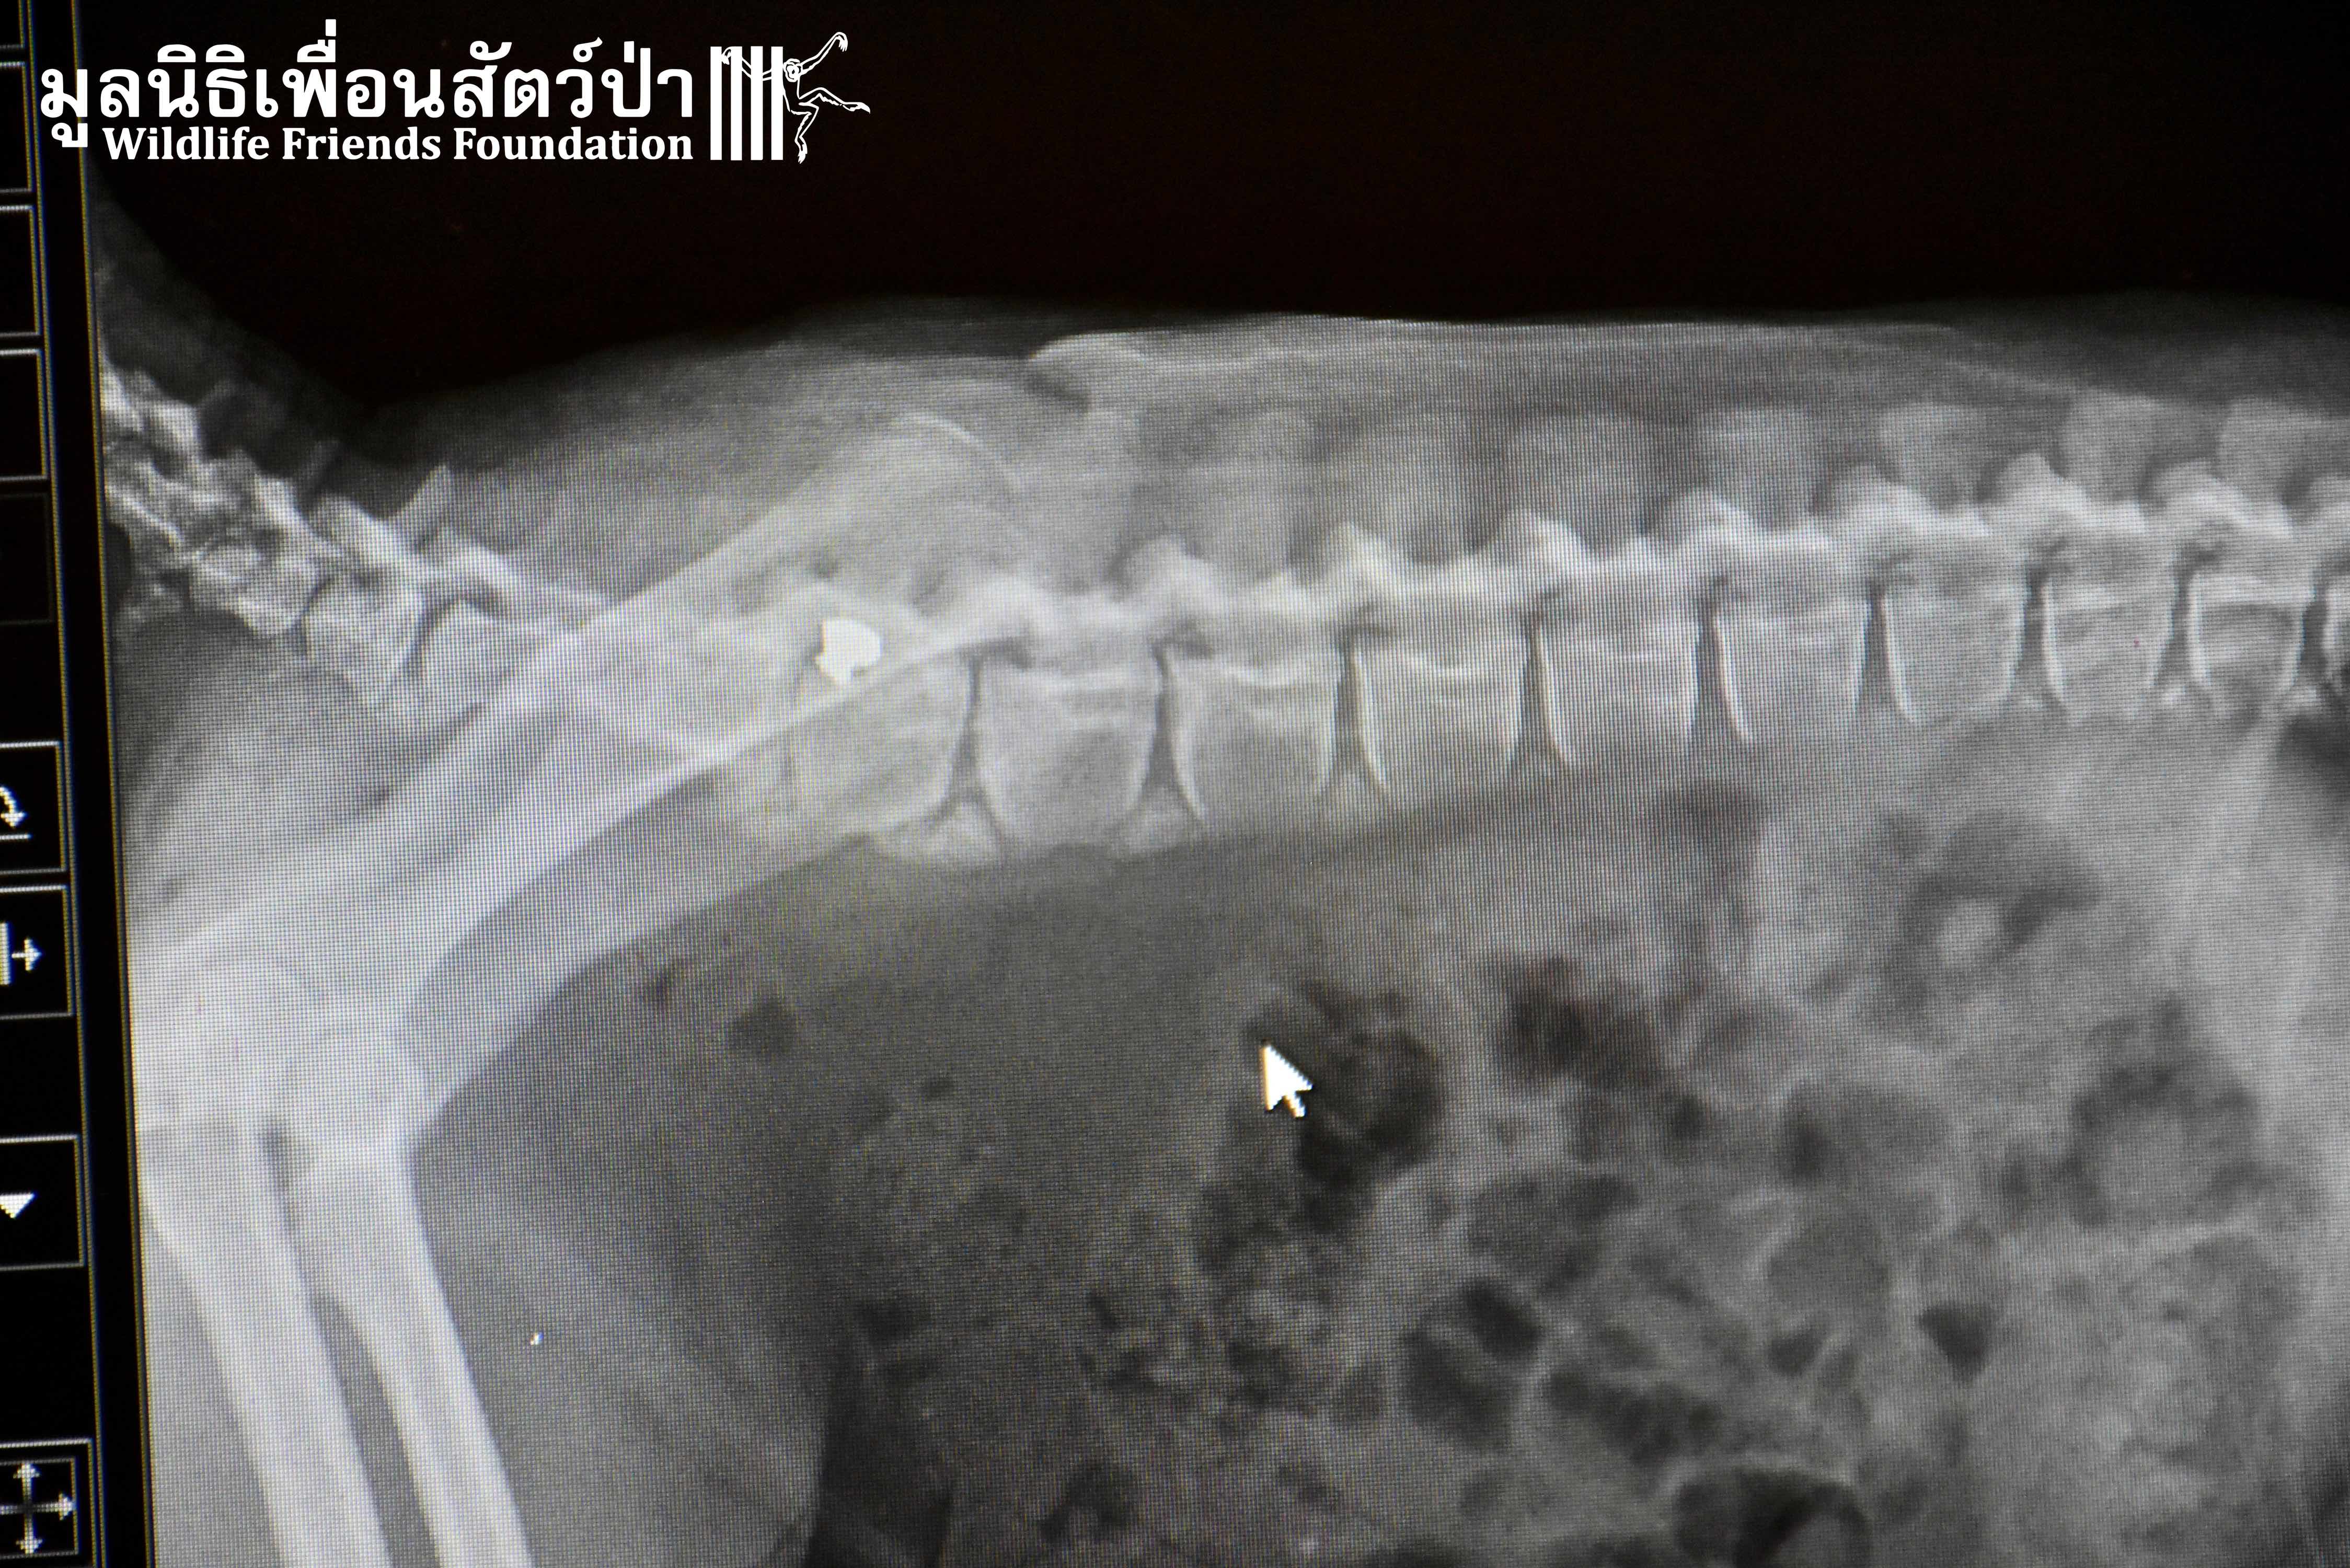

It was raining long-tailed macaques (Macaca fascicularis) in the hospital this week! Our first patient, Auan, arrived 2 months ago after being hit by a car. Although no breaks or dislocations were found, his radiographs revealed four old bullets lodged in his spine, thigh, ankle, and arm. His right leg suffered additional extensive abrasions from the car accident. Our hospital staff surmise that he has nerve damage that led to him painlessly dragging around his disabled limb, thus getting it infected. We decided to amputate this leg to avoid further complications. Because he is a large adult male, we are hopeful that he can be successfully released after he recovers and passes observation in quarantine.